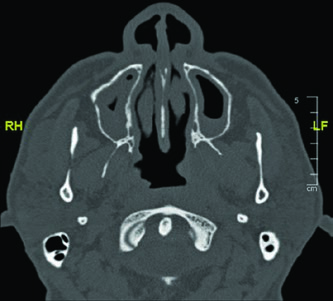

The CT images demonstrate the glossopharyngeal nerve pathway through different axial slices. The nerve can be identified posterolateral to the styloid process, descending alongside the internal carotid artery. The red oval marking across slices indicates the expected nerve location along its cervical course. The final slice uses soft tissue windowing for improved visualization of the relationship between the nerve and cervical vessels.

Mastering this anatomy is especially relevant when planning radiation for parotid adenoid cystic carcinomas, given their strong tendency to follow nerve sheaths. Including the full course — from the jugular foramen to the pharyngeal branches — ensures that subclinical spread along the glossopharyngeal nerve is adequately covered. A similar neural mapping approach is discussed in the context of unknown primary tumors of the head and neck.